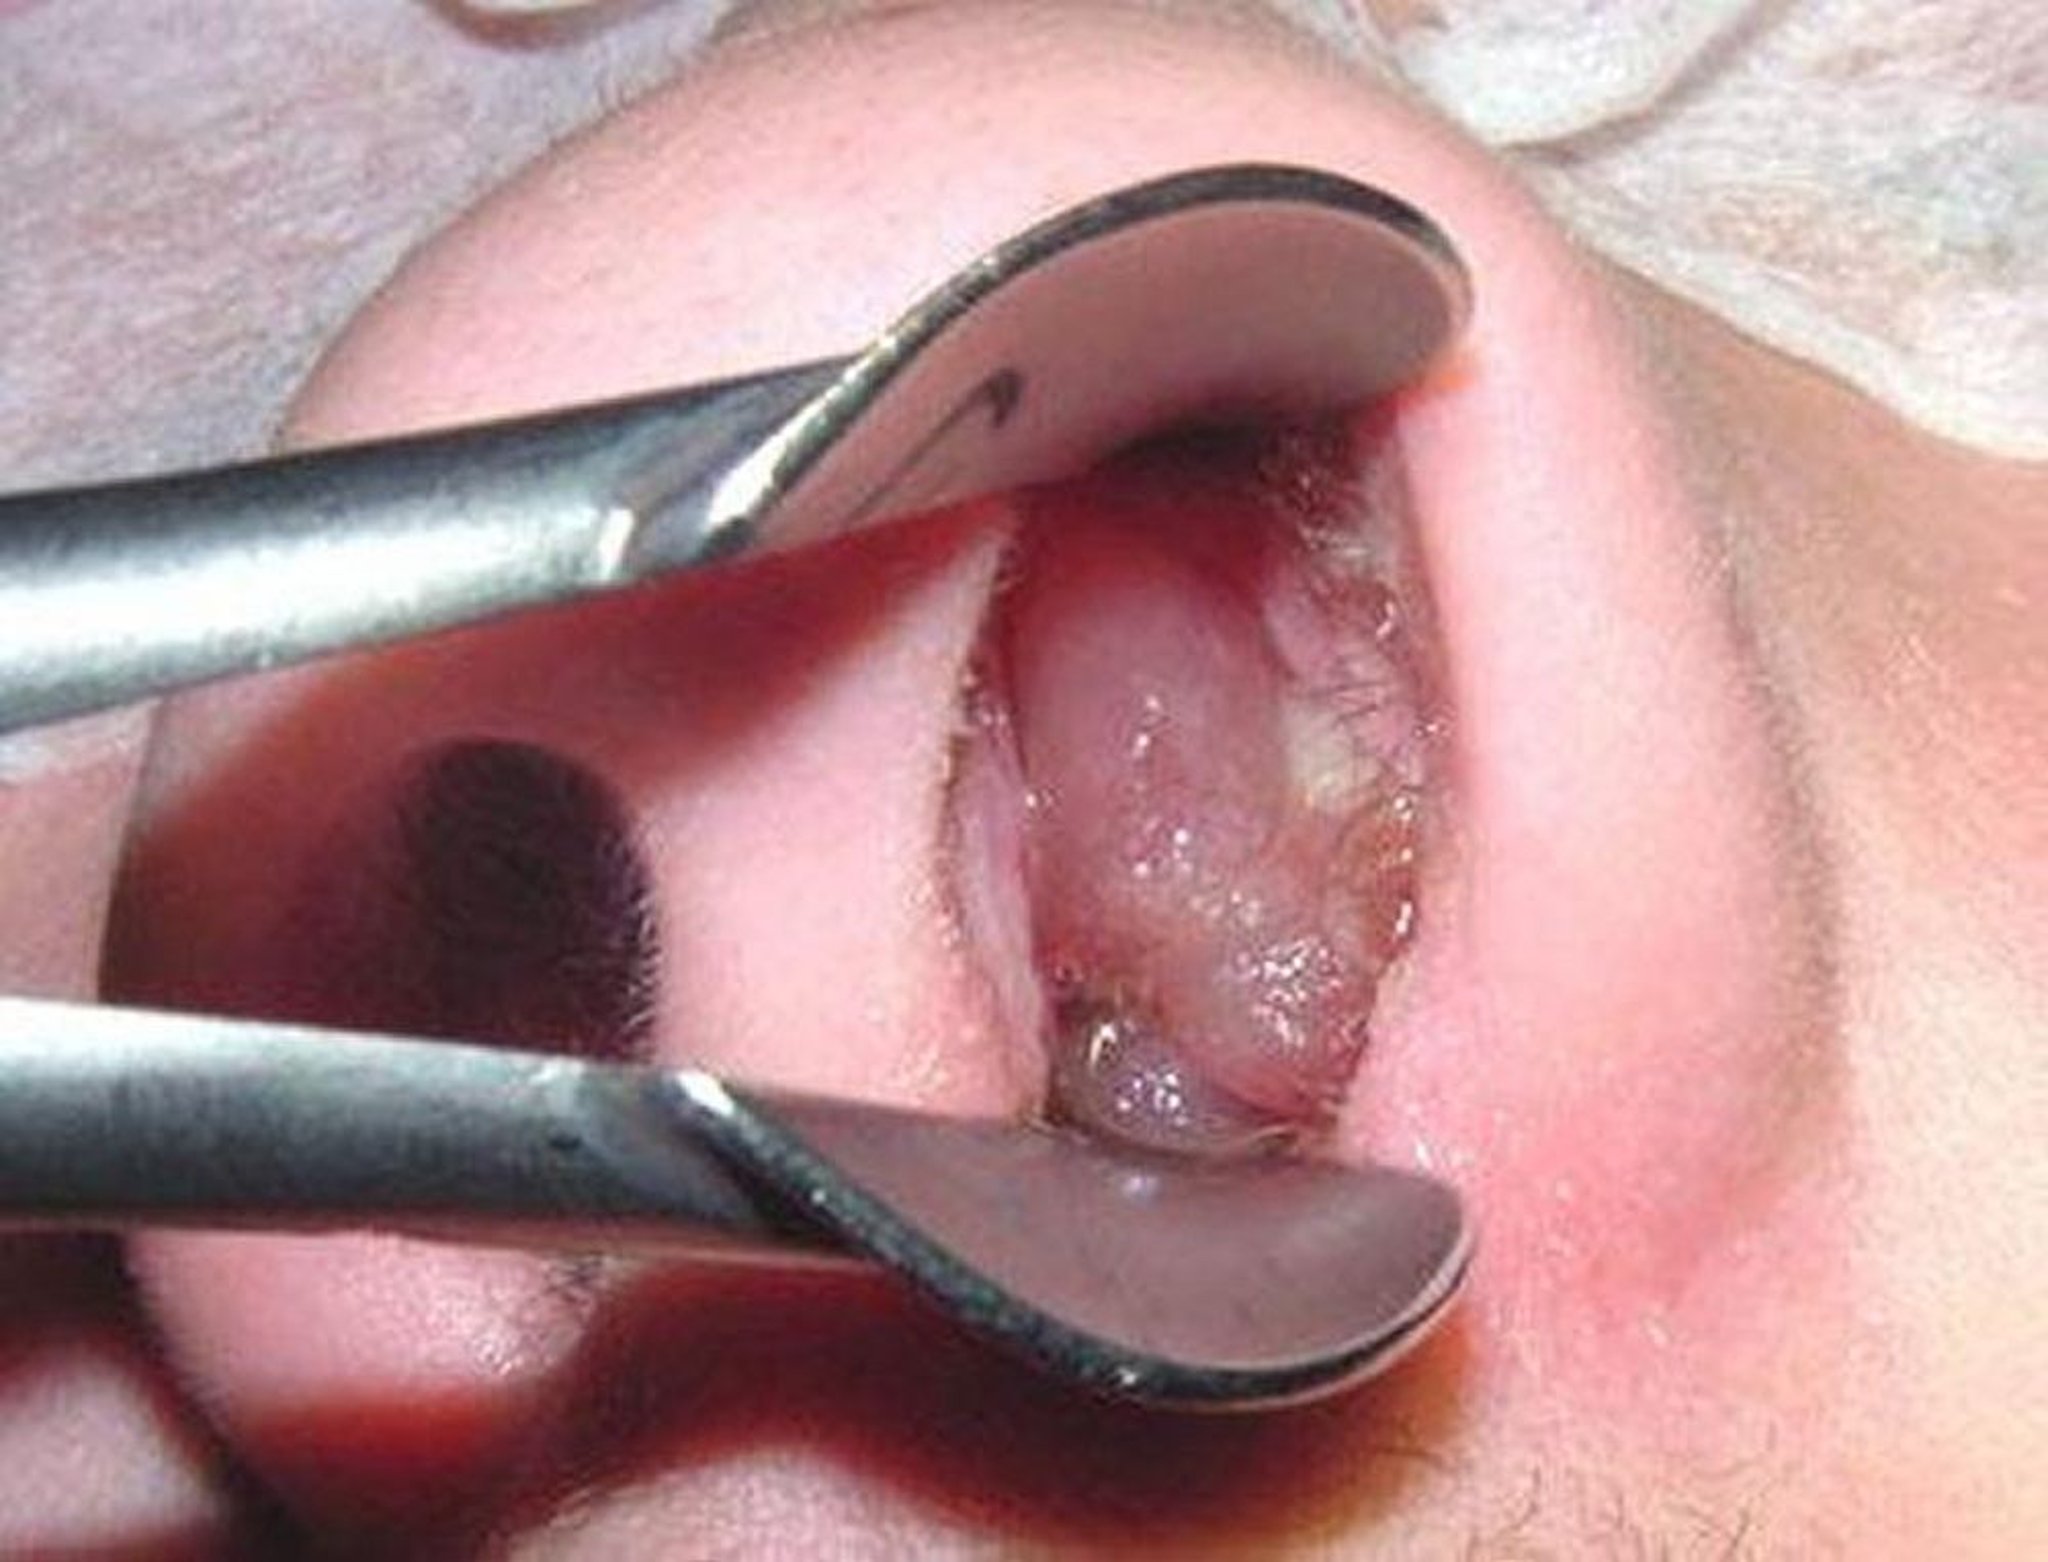

Polip hidung matang dapat menyerupai anggur tanpa biji yang dikupas.

Gambar disediakan oleh Bechara Ghorayeb, MD.